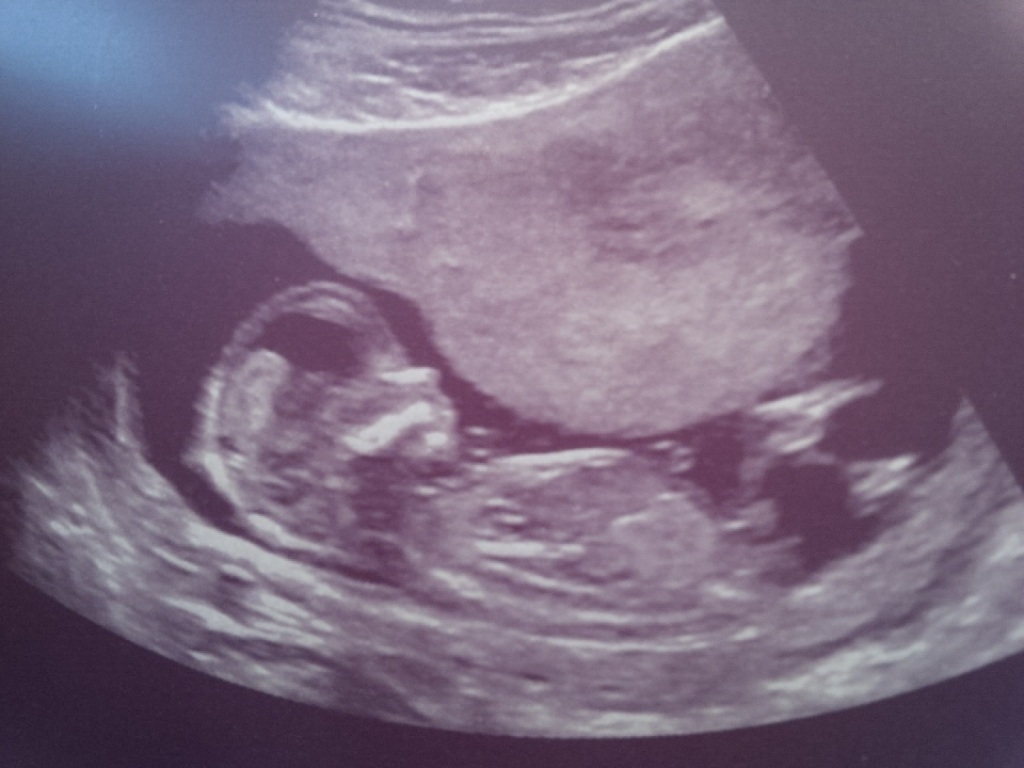

Boy:)

Boy

You look at the area right below the leg, where the leg is attached to the body. Directly under that, (sorta sticking out of the body) there is a blob-looking thing that when you look carefully, you can see is two sorta lines, one stacked on top of the other (this is called a "stacked nub" and is seen in male fetuses). Additionally, if you look at the angle of that nub, compared to the angle of the spine, you can see that the nub is angled "upward," which is also indicative of a male fetus. My guess on this baby is boy.

There are various things you look for when looking for a girl as well. The area would be more of a straight line and would be coming directly out of the body, parallel to the spine. Sometimes you will see a fork (like this: --< ) at the end of a girl nub. But not necessarily and having a fork itself is not a sign of girl. It has to be paired with the angle of the nub to signify girl.

Most people learn to guess just by being on forums like this and studying various nubs and seeing the difference. Ive been guessing for over 2 years now. Some nubs still stump me. But this one is more classic.

Leaning boy

It does look like a boy Hopeful!